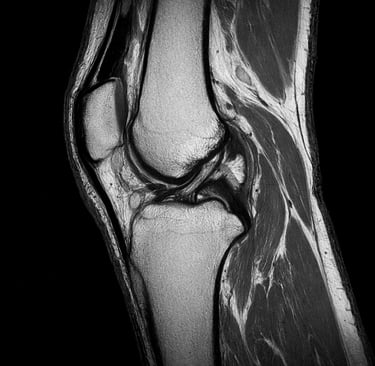

Examens complémentaires

Certains examens peuvent être prescrits :

échographie du genou

radiographie

IRM du genou

Ces examens permettent d’identifier la cause de la douleur.